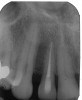

A 54-year-old, non-smoking woman presented with a root fracture at the maxillary right lateral incisor (Figure 1). The patient presented with a 10-mm pocket at the mid-facial probing depth, and a Grade 2 mobility. The preoperative peri-apical digital radiograph can be seen in Figure 2. A natural diastema existed on the distal aspect of the right maxillary incisor, and the patient did not wish to have this corrected. To hold the natural tissue emergence profiles throughout the treatment phase, the immediate implant placement and provisionalization procedure was chosen to treat the affected site. Before the procedure, an occlusal index and registration was taken so that when the retrofitting of the natural tooth shell was accomplished, the exact location of the natural tooth shell could be seated on the implant abutment at the time of implant placement (Figure 3). After administration of an appropriate local anesthetic, tooth No. 7 was removed by an atraumatic technique to preserve the natural soft tissue emergence profiles present pre-surgically (Figure 4). After tooth removal, debridement of the extraction socket was accomplished by curettage of the socket, followed by rotary instrumentation with a course #8 round diamond to ensure removal of all remnants of the periodontal ligament, granulation tissue, and localized debris. To aid in the debridement, the patient was started on a preoperative administration of Augmentin 875 mg, taken the day before treatment, and once again 1 hour before the surgical visit. The patient then continued this antibiotic course for a total of 10 days.

Figure 2  Pretreatment peri-apical radiograph.

Figure 2